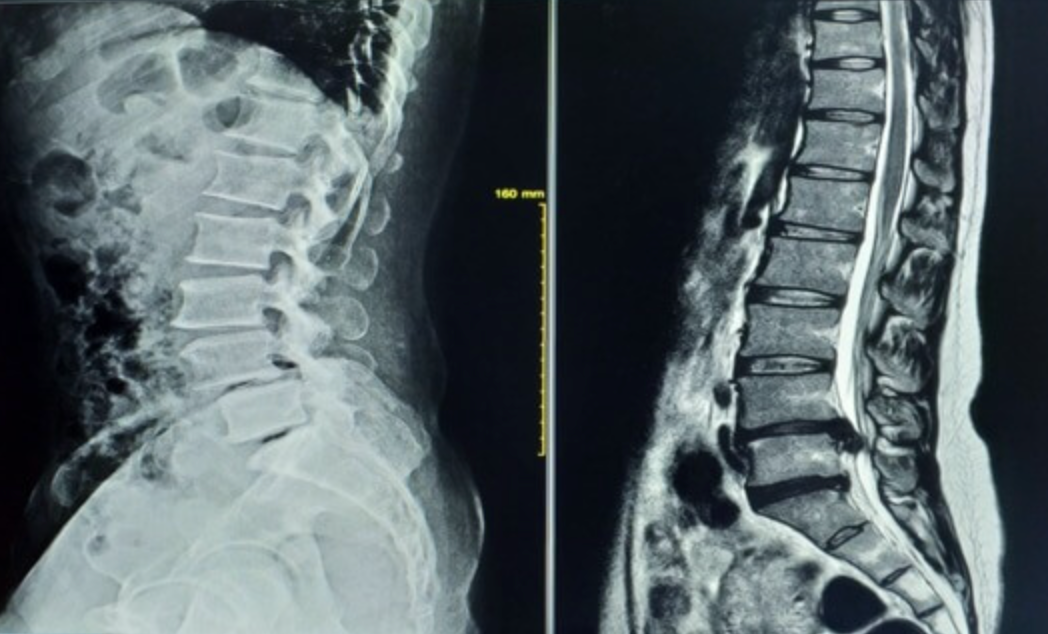

肩こりの根本改善はマッサージではなく、頸椎の配列を整えることが大切 多くの人が抱える「肩こり」。疲れやストレスのたびにマッサージや揉みほぐしに頼っていませんか?確かにその場の痛みや張り感は和らぎますが、根本的な改善にはつ […]